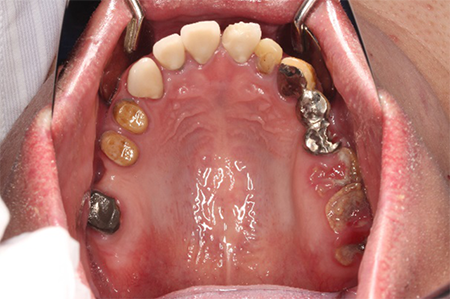

この患者様は長い事歯科医院には通っておらず、下の歯は前歯以外は全て崩壊していることが分かります。

前から見ても歯が欠けてしまい、歯茎も赤く腫れてしまっているのが分かります。

一般的には入れ歯が妥当かと思われますが、患者様は33歳、まだまだ人生は長いです。

奥歯がないと前歯でしか噛めなくなってしまい、残っている前歯もいずれダメになってしまいます。

また、奥歯がなくなってからの期間が長かったため、入れ歯が入るスペースが奥にないのが分かります。

様々なことを鑑み、患者様とも何度も話し合いを行い、下の奥歯には必要最低限のインプラントを、他の歯も外科処置を施しなるべく歯を抜かない方法を取りました。

最終的に抜歯した本数は下の歯5本。上の歯に関しては全て残すことが出来ました。

奥歯があることで前歯の負担を減らし、前歯を失うリスクを下げることが出来ます。